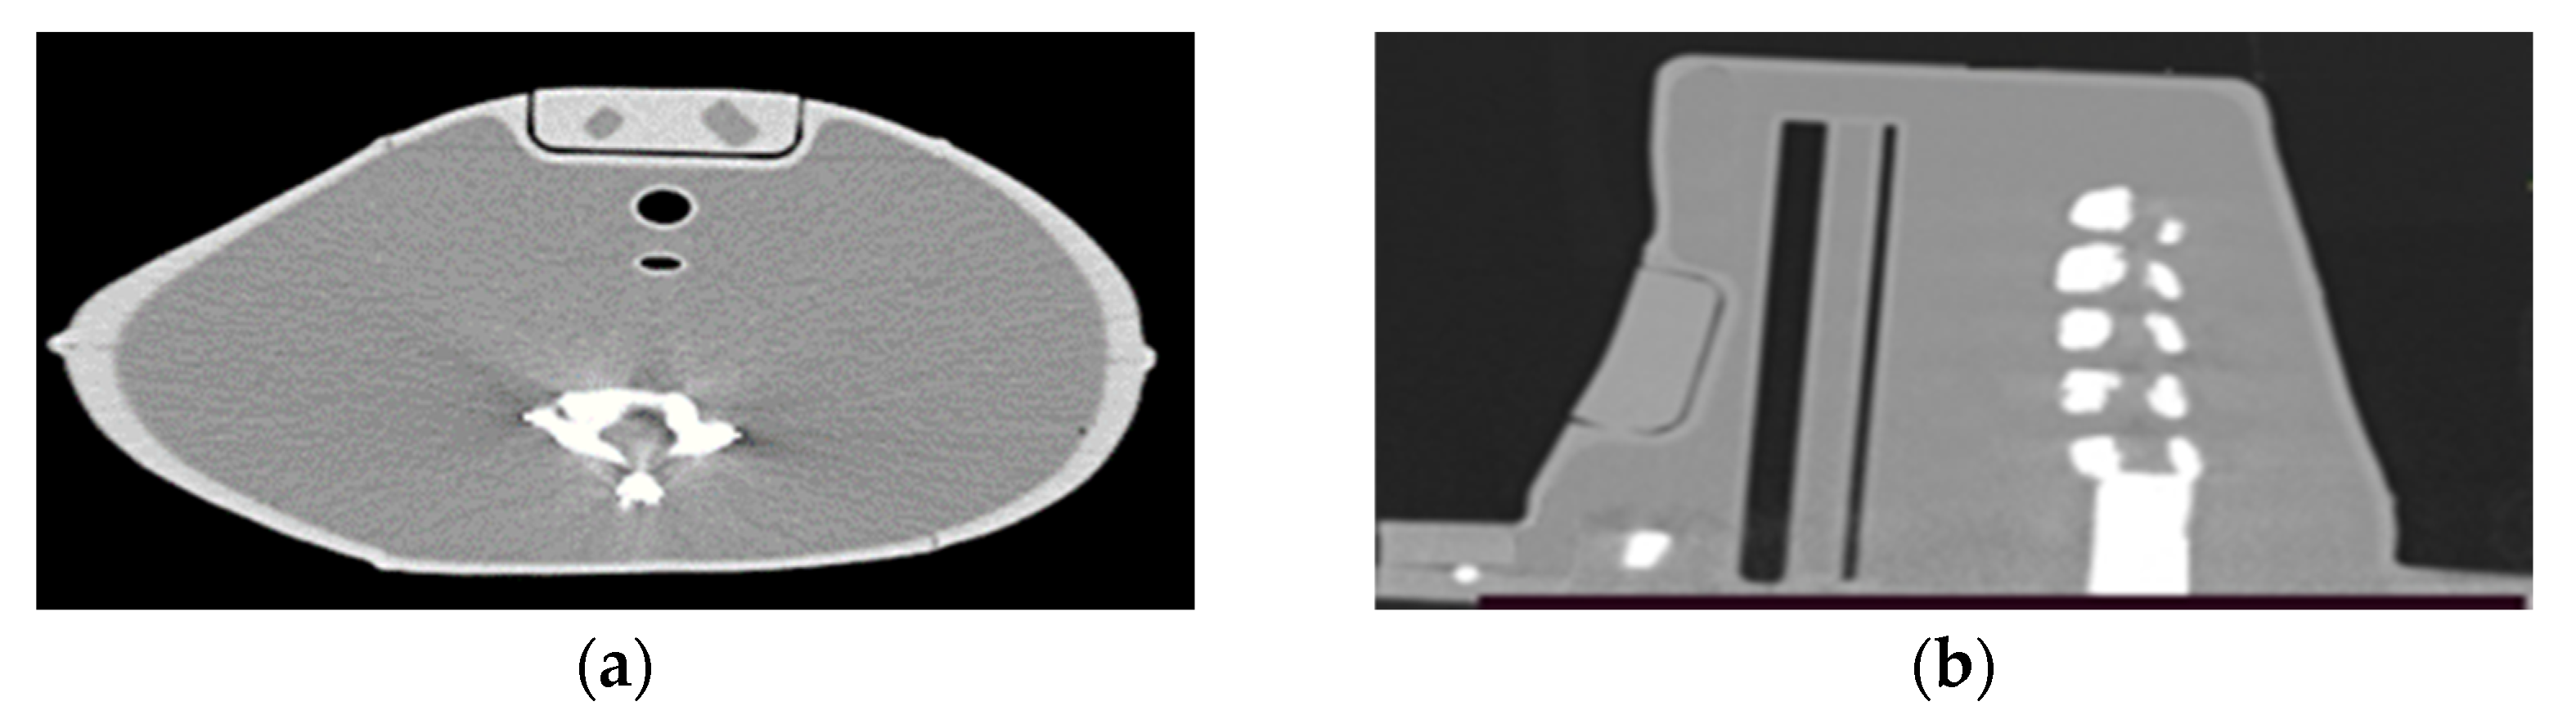

Figure 14 shows the I-131 and I-123 TEW scatter corrected SPECT/CT images of the custom-made phantom with 1.5- and 3-mL remnants. In both acquisitions, the administered I-131 and I-123 activities within the remnants were 13 MBq. An experienced nuclear medicine physician visually evaluated the images. Less spillover of activity and better uniformity were observed on the I-123 than the I-131 images. The physician was more confident in deciding the volume of remnants from I-123 than I-131 images.

Figure 14. The TEW scatter corrected (left) I-131 and (right) I-123 SPECT/CT images using the custom-made phantom with 1.5- and 3-mL thyroid remnants. In both acquisitions, the administered I-131 and I-123 activities within the remnants were 13 MBq.